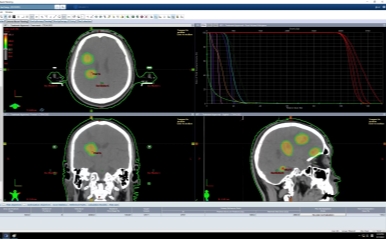

(1)头部立体定向放疗(SRS)

六安市中医院肿瘤放疗科团队运用最先进的立体定向放疗专业设备——Edge医用直线加速器(速锋刀)搭载的最新的“超弧刀”HyperArc高解析度放射外科治疗技术,采用“一键式”非共面放射外科技术,对于精准放射治疗要求很高的颅内多发肿瘤,可实现高质、高效、无创的放射外科治疗,为广大脑部肿瘤患者带来了新的希望。

采用HyperArc技术一次性可以治疗多个病灶同时对正常组织的保护更好

HyperArc高解析度放射外科治疗病例展示